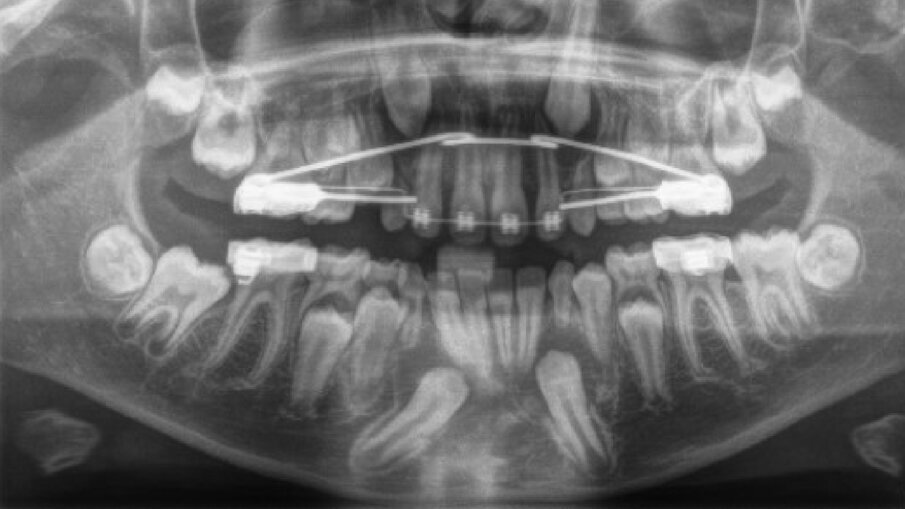

Il paziente, maschio, di 10 anni e mezzo, in dentizione mista. Le arcate dentarie sono in prima classe molare e canina. È presente un overjet di 1 mm e le linee mediane sono centrate. Si osserva un leggero affollamento in entrambe le arcate. Viene raccolta tutta la documentazione clinica per la valutazione del caso ed il successivo trattamento. Si procede alla presa delle impronte per i modelli da studio (Fig. 2). Vengono effettuate l’RX OPT (Fig. 3), la teleradiografia latero-laterale del cranio (Fig. 4) e l’analisi cefalometrica (Fig. 5, Tab. 1). Dopo un anno di terapia intercettiva, è stato eseguito un controllo con una rx OPT per valutare lo stato della permuta dentaria (Fig. 6). All’RX OPT si osserva l’inclusione intraossea con mesio versione dell’elemento 4.3. La CBCT è stata eseguita per valutare la posizione dell’CMI rispetto alle strutture anatomiche vicine (Fig. 7). Il CMI è stato valutato secondo la classificazione di Mupparapu5 nel tipo numero 1. Nella CBCT si osserva parte della corona del 4.3 a contatto con gli apici delle radici degli incisivi inferiori (4.1 e 4.2).

Fig. 3_RX OPT prima del trattamento ortodontico.

Fig. 6_RX OPT con inclusione dell’elemento 4.3.